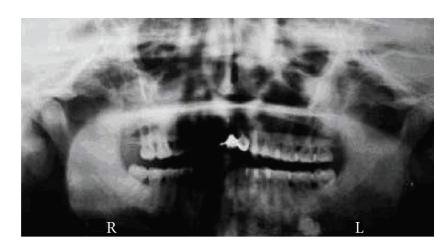

Gardner's syndrome (GS) is a dysplasia characterized by neoformations of the intestine, soft tissue, and osseous tissue. Endocrine neoplasms have occasionally been reported in association with GS. Adrenal masses in GS are rare, and few have displayed clinical manifestations. In the current paper, The authors report a 37-year-old male patient with GS including familial adenomatous polyposis (FAP) and mandible osteoma who presented with an incidental adrenal mass. Computerized tomography adrenal scan identified bilateral masses. Functional analyses showed a hormonal secretion pattern consistent with pre-Cushing's syndrome. Other extraintestinal manifestations were hypertrophy of the pigmented layer of the retina and histiocytofibroma in the right leg. This paper describes a rare association of adrenocortical secreting mass in an old male patient with Gardner syndrome.

加德纳综合征(GS)是一种发育异常,其特征为肠道、软组织和骨组织出现新生物。内分泌肿瘤偶尔会与GS相关联报告。GS患者出现肾上腺肿块的情况罕见,且很少有出现临床表现的。在本文中,作者报告了一名37岁男性GS患者,其患有家族性腺瘤性息肉病(FAP)和下颌骨骨瘤,偶然发现肾上腺肿块。肾上腺计算机断层扫描显示双侧有肿块。功能分析显示激素分泌模式与库欣综合征前期一致。其他肠道外表现为视网膜色素层肥厚和右腿组织细胞纤维瘤。本文描述了一名老年男性加德纳综合征患者罕见地出现肾上腺皮质分泌性肿块的情况。